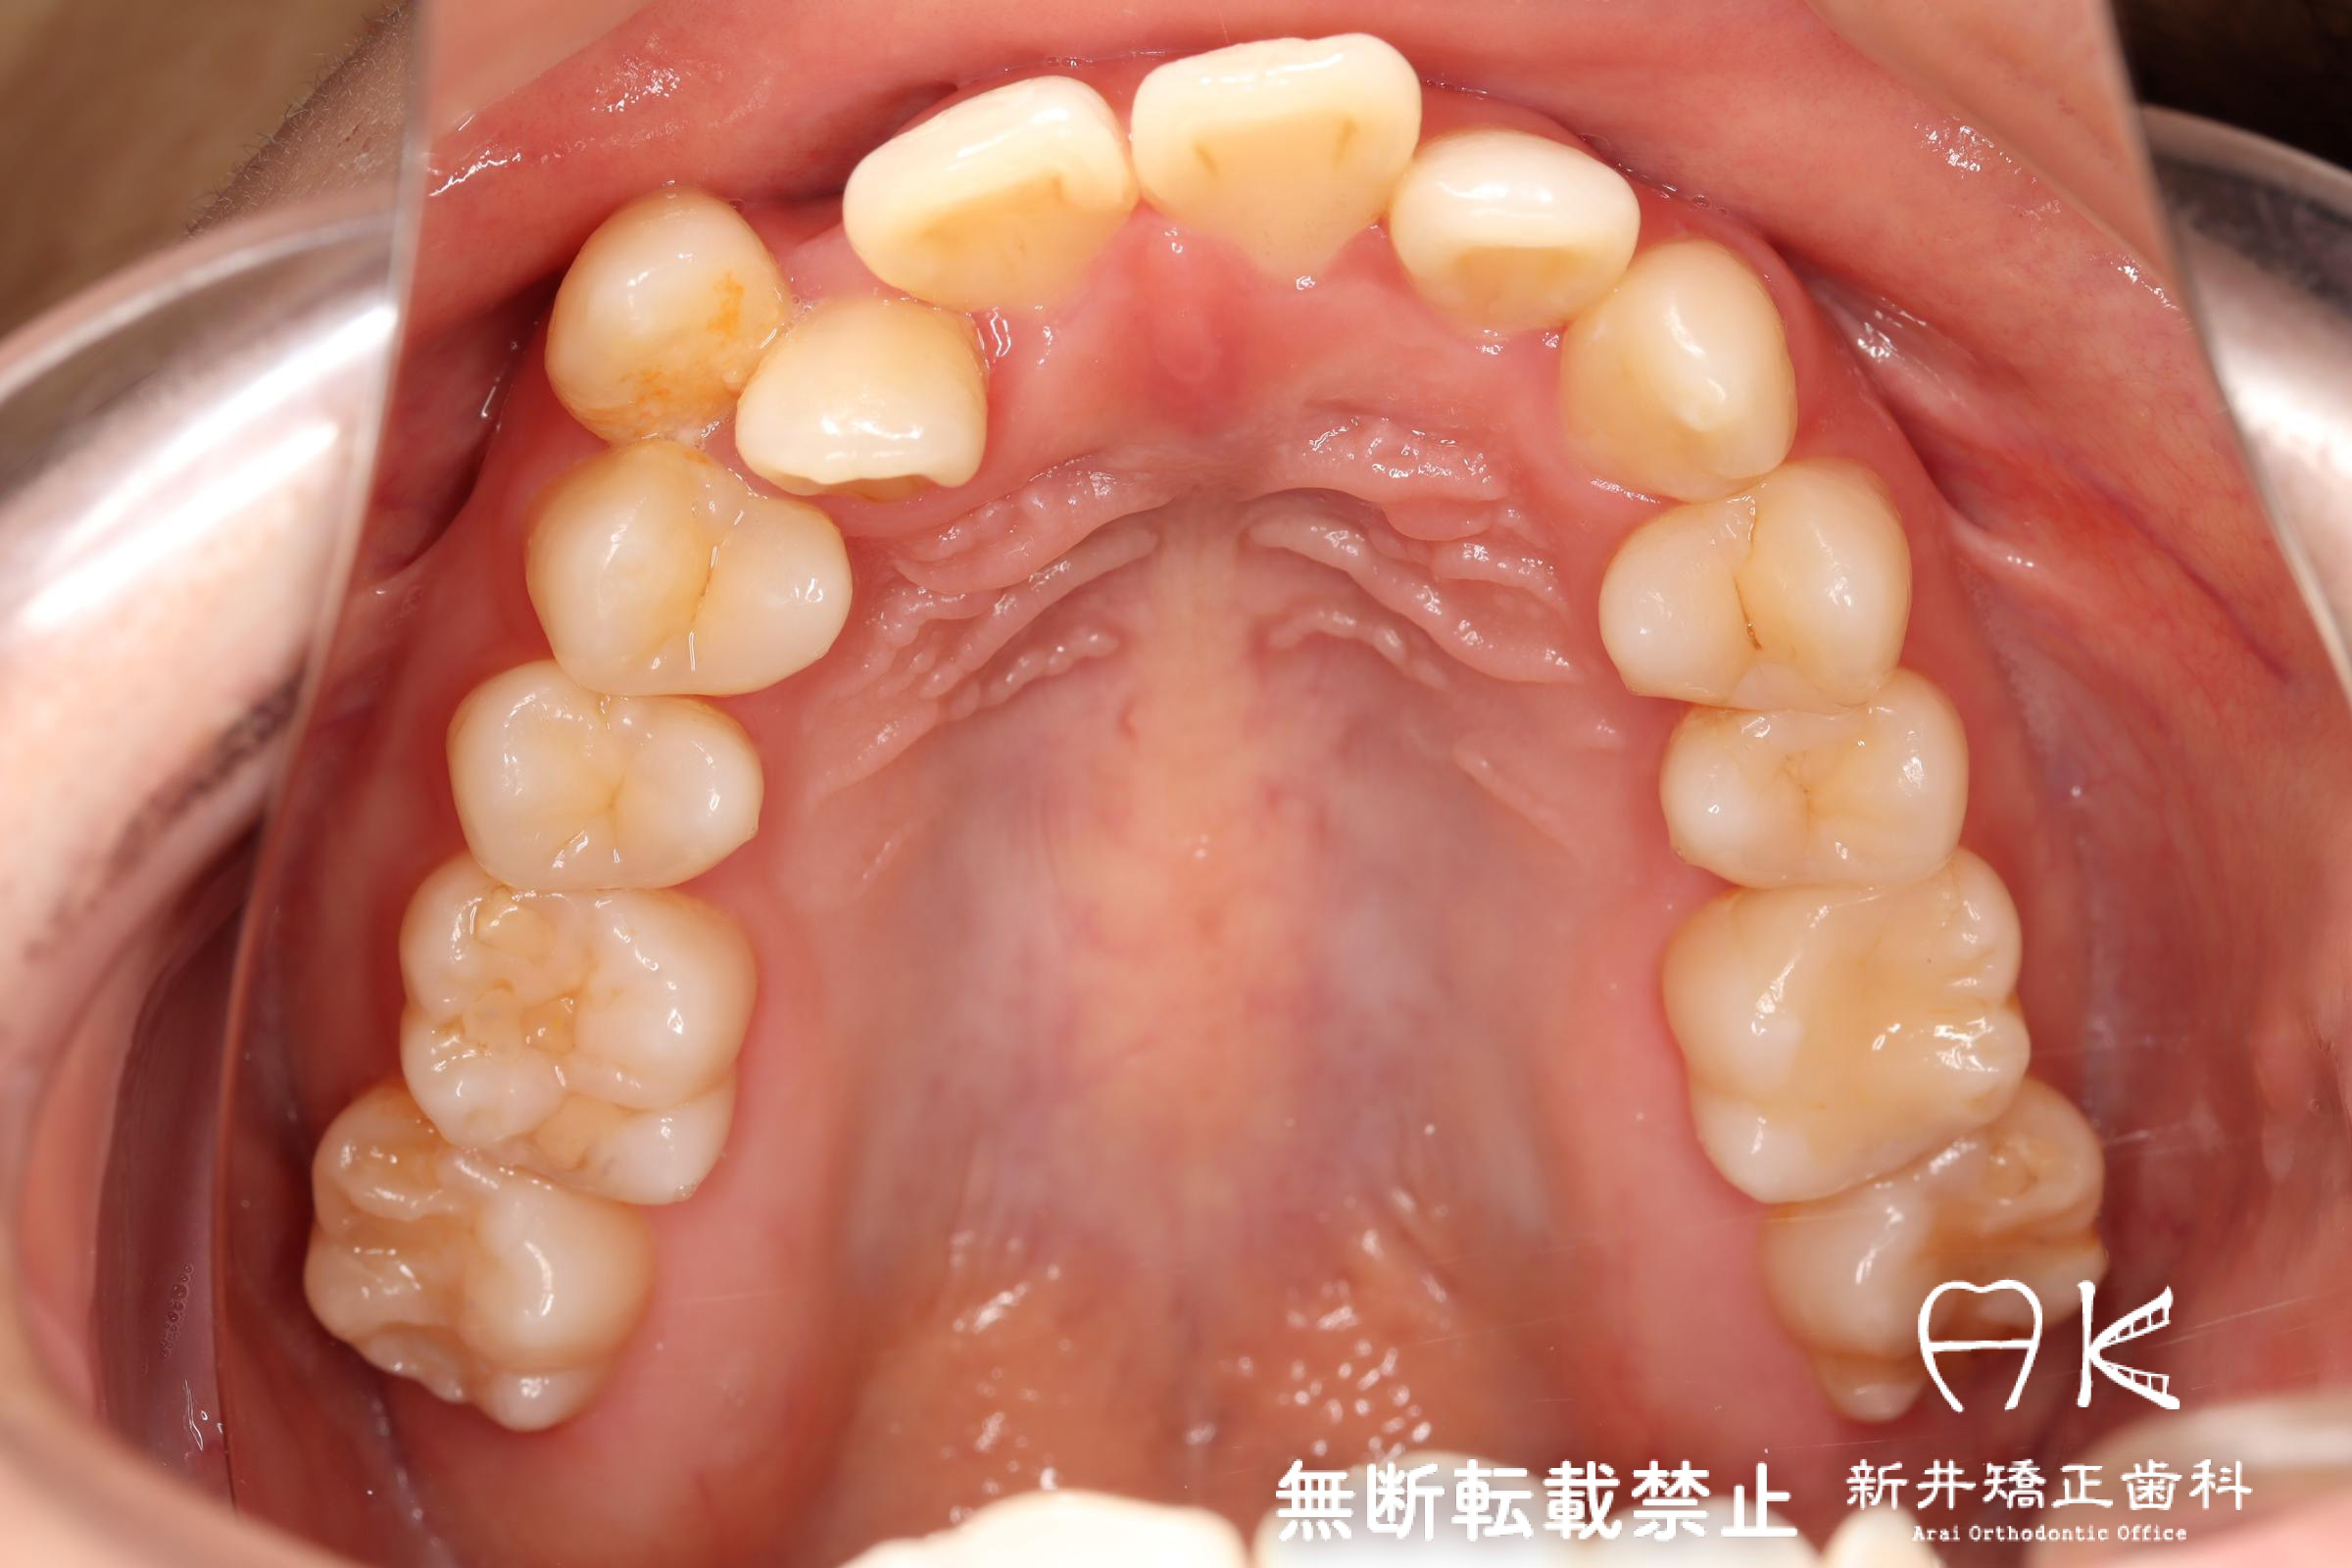

治療前後の解説

| 治療前 | 骨格的には受け口の患者さんですが、上顎前歯の唇側傾斜が大きく、患者さんとしては出っ歯だと思われていたパターンです。 元々口元の突出感はほとんどなかったため、歯を抜かずに上下顎ともに歯列を後方に移動させることにより主訴を改善させることとしました。 |